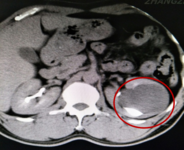

- 46岁的林先生最近比较烦恼,左侧肾脏长了个囊肿直径达8cm,医生告诉他如果不做手术,就有可能因剧烈活动或腰部外伤导致肾囊肿破裂,引发出血可危及生命。 经过慎重考虑,林先生求诊于漳州市中医院泌尿外科,接诊医生为陈惠新副主任医师。林先生的囊肿长在了肾盂的旁边,术语叫肾盂旁囊肿,周围被肾脏的实质严密包围着,稍有不慎就会损伤大血管引起大出血,危及生命。 为了确保手术顺利实施,泌尿外科全体医师对手术方式、术中可能出现的问题及应...发布时间:2020-06-30